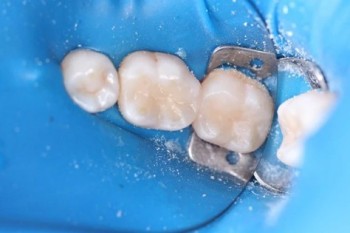

Кхалил Абаноуб Адли Абдуллах: портфолио (4)